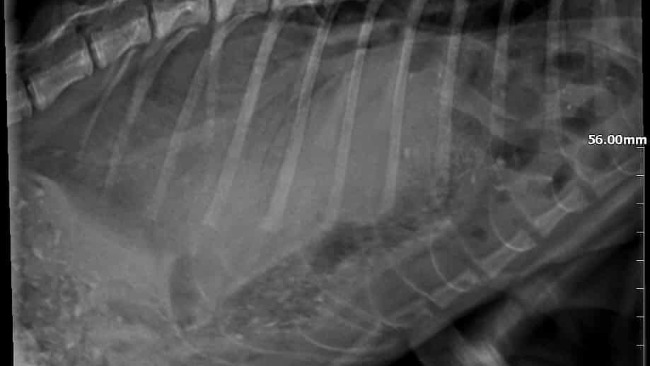

Ale mała ma ogromną wolę życia i powoli dochodziła do siebie, chociaż przez ten czas (a było to kilka tygodni) żyła w ogromnym bólu. Kiedy wreszcie trafiła do lekarza, badania wykazały przepuklinę przeponową — część narządów z jamy brzusznej przemieściła się do klatki piersiowej, utrudniając jej oddychanie.